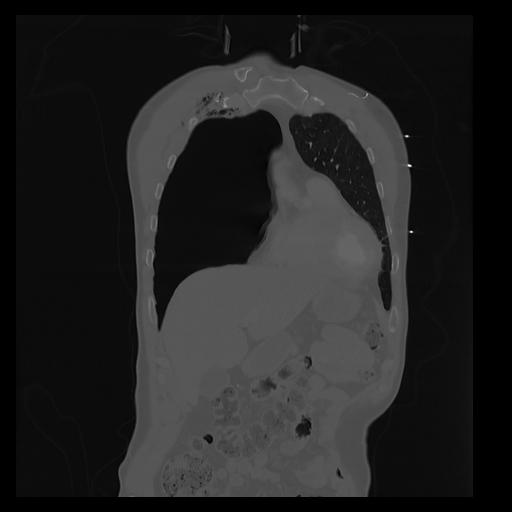

32 PULMON,CE,Coronal,3.000,PULMON,Coronal,